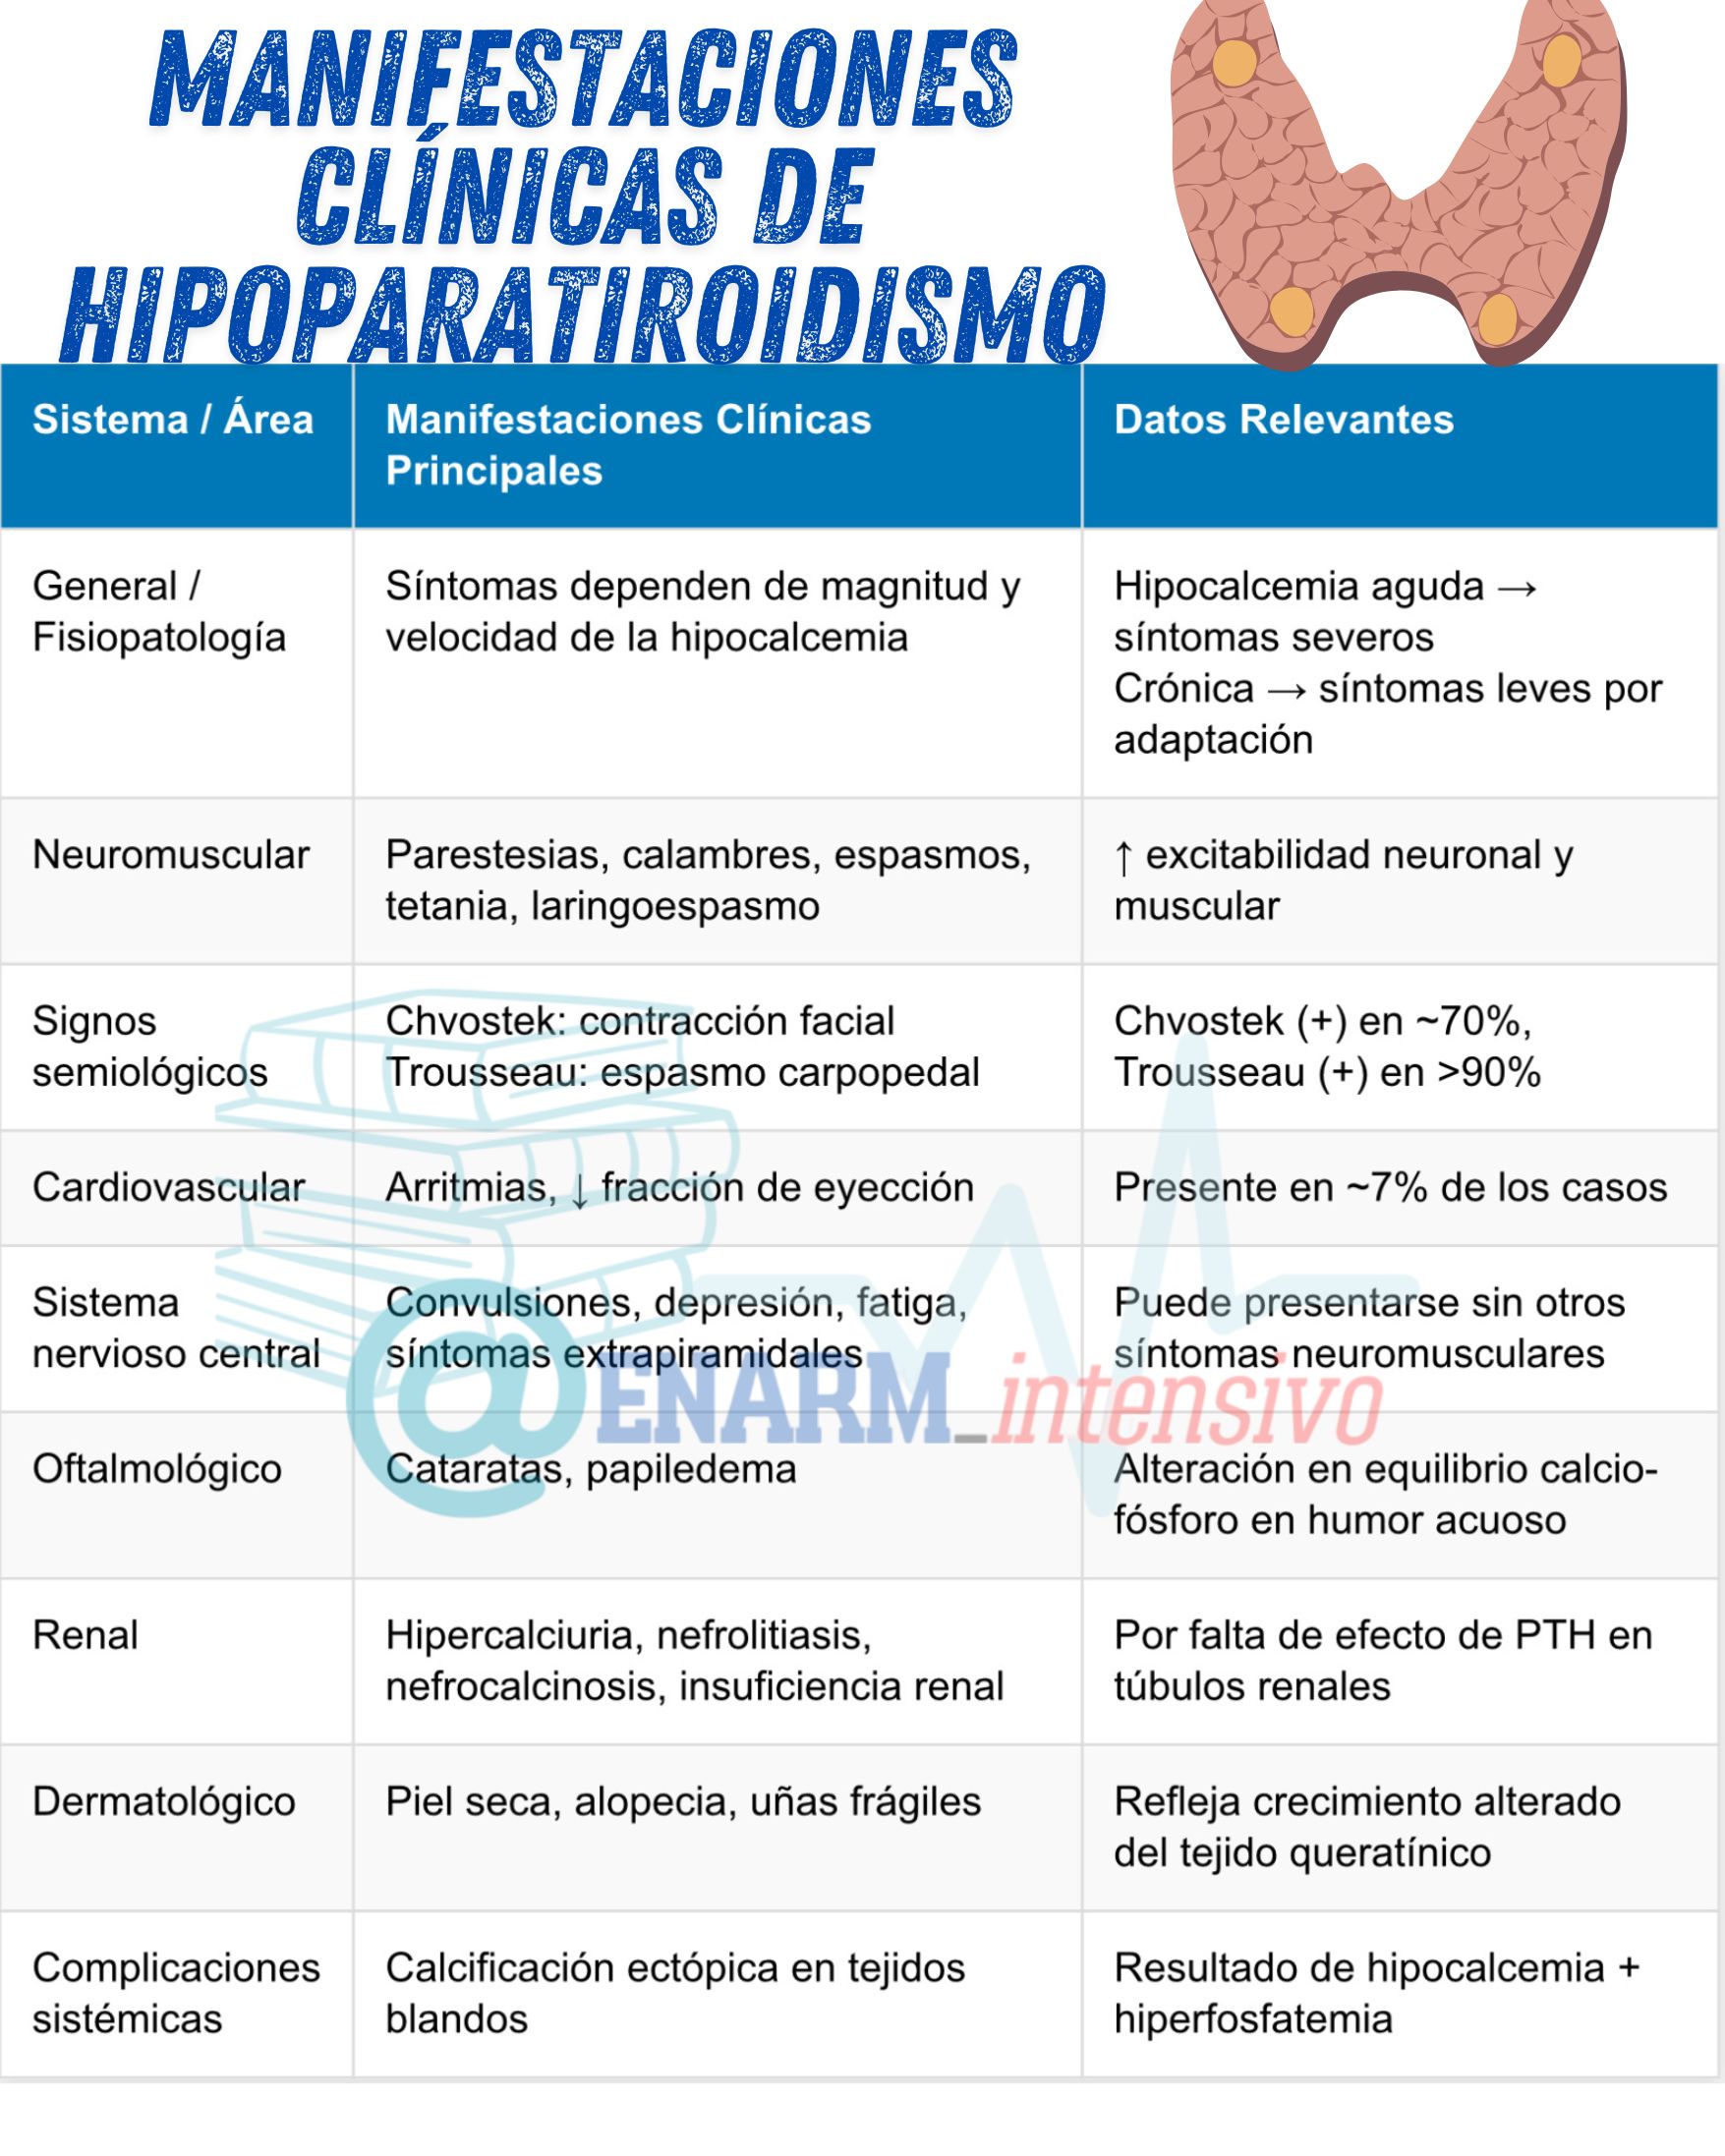

Manifestaciones clínicas

Los síntomas del hipoparatiroidismo dependen de dos factores fundamentales: la magnitud del descenso del calcio sérico y la velocidad con la que ocurre esta disminución. Esta relación dinámica entre la concentración de calcio y la adaptación fisiológica del organismo explica por qué pacientes con hipocalcemia aguda pueden presentar síntomas graves aun cuando los niveles de calcio en sangre se encuentren solo ligeramente reducidos o incluso dentro del rango bajo-normal. En contraste, pacientes con hipocalcemia crónica y severa, desarrollada de forma lenta y progresiva, pueden exhibir escasa sintomatología o manifestaciones clínicas poco evidentes, debido a mecanismos compensatorios que atenúan la respuesta neuromuscular y sistémica a la deficiencia de calcio.

Desde el punto de vista neuromuscular, la hipocalcemia inducida por hipoparatiroidismo se caracteriza por un aumento de la excitabilidad de las membranas neuronales y musculares. Esta hiperexcitabilidad se traduce clínicamente en irritabilidad neuromuscular, que se manifiesta por parestesias, especialmente en la región perioral y en las extremidades distales (manos y pies), mialgias, calambres musculares, espasmos musculares generalizados y, en casos severos, tetania. El reflejo osteotendinoso puede encontrarse exacerbado, y en casos críticos puede producirse laringoespasmo, una contracción súbita de la musculatura laríngea que obstruye parcialmente la vía aérea, causando estridor respiratorio, una condición potencialmente peligrosa si no se reconoce y se trata de forma oportuna.

Existen signos clínicos semiológicos clásicos que orientan al diagnóstico de hipocalcemia, como el signo de Chvostek y el signo de Trousseau. El signo de Chvostek consiste en la contracción involuntaria de los músculos faciales al percutir el nervio facial frente al trago; se encuentra presente en aproximadamente el setenta por ciento de los pacientes con hipocalcemia, pero también puede observarse en un pequeño porcentaje de individuos normocalcémicos. Por otro lado, el signo de Trousseau, mucho más específico, se observa en más del noventa por ciento de los individuos con hipocalcemia y en menos del uno por ciento de los individuos sin alteraciones del calcio. Este signo se desencadena al inflar un manguito de presión arterial por encima de la presión sistólica durante varios minutos, lo que induce una contracción característica de la mano y la muñeca (espasmo carpopedal), producto del aumento de la irritabilidad neuromuscular en condiciones de hipocalcemia.

A nivel cardiovascular, la hipocalcemia aguda puede provocar arritmias, presentes en aproximadamente el siete por ciento de los casos. Estas alteraciones incluyen bradicardia, arritmias ventriculares y disminución de la fracción de eyección, reflejo de una disfunción miocárdica inducida por el desequilibrio iónico. Dado que el calcio es fundamental para la contractilidad cardíaca y la conducción del impulso eléctrico, su deficiencia puede alterar profundamente la función cardiovascular.

Las manifestaciones del sistema nervioso central también son frecuentes y variadas. Entre las más relevantes se encuentran las convulsiones, que ocurren en alrededor del once por ciento de los pacientes, incluso en ausencia de otros signos de irritabilidad neuromuscular. También pueden presentarse alteraciones del estado de ánimo, tales como depresión (observada en el doce por ciento de los casos), irritabilidad, fatiga, alteraciones cognitivas, y síntomas psiquiátricos más complejos. En algunos casos, se han descrito síntomas extrapiramidales, lo que sugiere que la hipocalcemia prolongada puede afectar el metabolismo de regiones cerebrales profundas involucradas en el control motor.

En el ámbito oftalmológico, el hipoparatiroidismo crónico puede dar lugar a la formación de cataratas, presentes en aproximadamente el diecisiete por ciento de los casos. Esta opacificación del cristalino se debe a alteraciones en el equilibrio de calcio y fósforo dentro del humor acuoso. En casos de hipocalcemia severa, también puede desarrollarse papiledema, una inflamación del nervio óptico que refleja un aumento en la presión intracraneal secundaria a cambios en la permeabilidad vascular cerebral.

Las manifestaciones renales del hipoparatiroidismo crónico están estrechamente relacionadas con la hipercalciuria. A pesar de los bajos niveles séricos de calcio, la excreción renal puede estar aumentada debido a la ausencia del efecto regulador de la hormona paratiroidea sobre el túbulo distal renal. Esto conduce a complicaciones como nefrolitiasis (formación de cálculos renales), nefrocalcinosis (depósito de sales de calcio en el parénquima renal), presentes en un quince por ciento de los pacientes, y en algunos casos, insuficiencia renal crónica, observada en el doce por ciento de los casos.

Desde el punto de vista dermatológico, la deficiencia crónica de hormona paratiroidea con hipocalcemia persistente se asocia con signos cutáneos visibles. La piel suele volverse seca y áspera, el cabello presenta sequedad y puede observarse alopecia tanto en el cuero cabelludo como en las cejas. Las uñas pueden volverse quebradizas y desarrollar surcos transversales, lo que refleja un crecimiento alterado del tejido queratínico.

La combinación de hipocalcemia crónica con hiperfosfatemia —otra consecuencia típica del hipoparatiroidismo— favorece la precipitación de fosfato cálcico en tejidos blandos. Esta calcificación ectópica puede afectar articulaciones, piel, vasos sanguíneos y otros órganos, comprometiendo su función y generando complicaciones sistémicas progresivas.